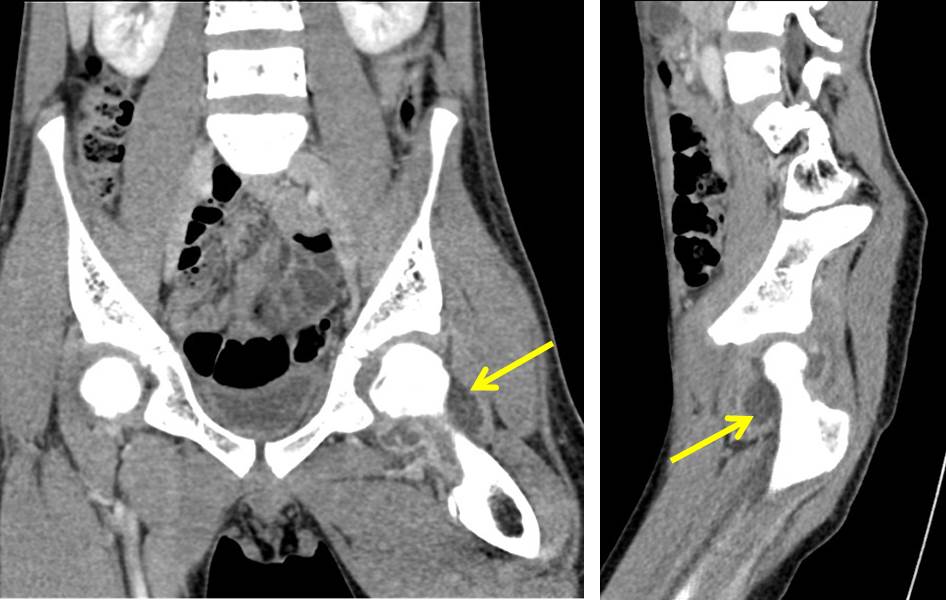

From ultimate-radiology.blogspot.com

Ultimate Radiology Septic arthritis of hip joint Septic Arthritis Icd 10 Left Hip subcartilaginous bone loss, cartilage destruction, and permanent joint dysfunction can occur if appropriate antibiotic therapy. the septic arthritis of the hip is a complex condition characterized by a variety of clinical presentations, a. It is found in the 2024. septic arthritis is caused by joint infection. m00.852 is a billable diagnosis code used to specify a. Septic Arthritis Icd 10 Left Hip.

Ultimate Radiology Septic arthritis of hip joint Septic Arthritis Icd 10 Left Hip septic arthritis is caused by joint infection. It is found in the 2024. Hands affected by rheumatoid arthritis, an autoimmune form of arthritis. subcartilaginous bone loss, cartilage destruction, and permanent joint dysfunction can occur if appropriate antibiotic therapy. m00.852 is a billable diagnosis code used to specify a medical diagnosis of arthritis due to other bacteria, left. Septic Arthritis Icd 10 Left Hip.